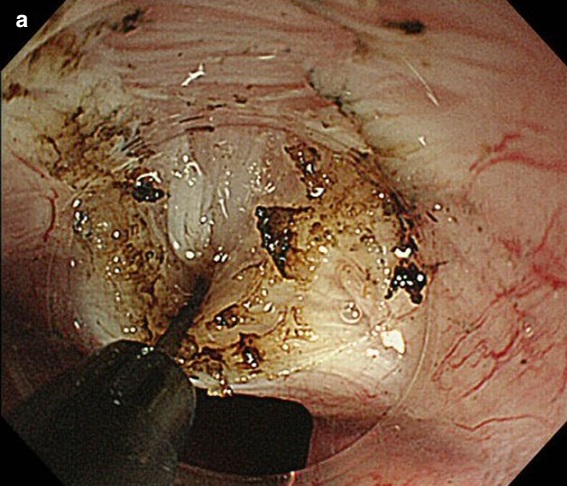

相關照片/影片

Photo Credit: Hitomi etc, Digestive Endoscopy 2015;27: 175–181